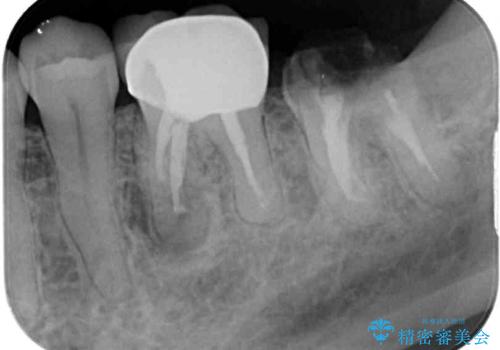

- 近医にて奥歯の抜歯が必要と言われたとのことで来院された患者様です。

診査の結果、歯が破折しており、抜歯が必要な状態でした。

インプラントにはストローマン社のSLActiveを使用し、埋入から補綴までおよそ3か月と、短期間で治療を進めることができました。